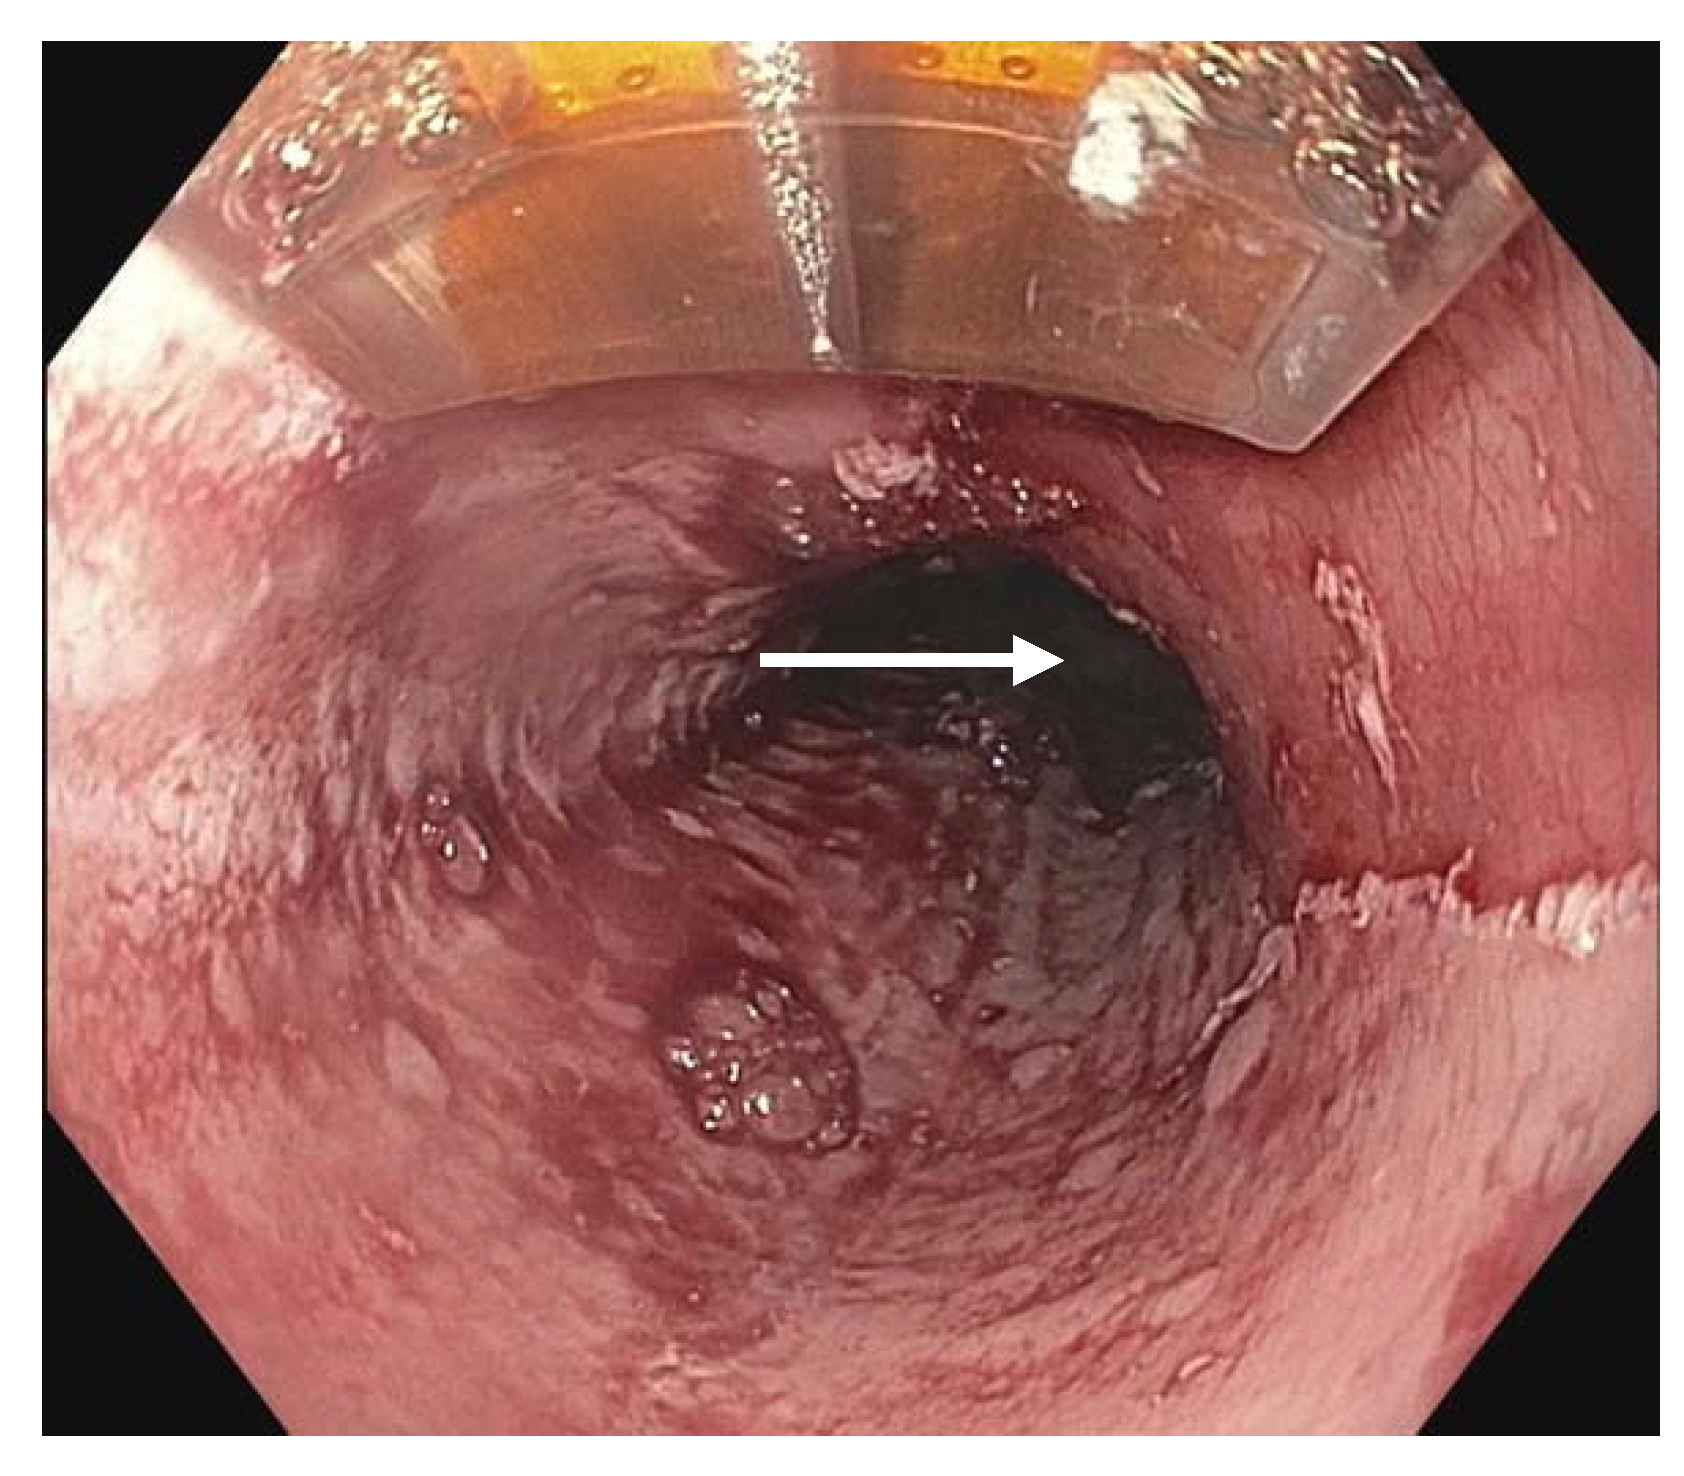

In addition to white light endoscopy, endoscopic ultrasound (EUS) and endoscopic mucosal resection (EMR) (Figure 2) are often performed prior to endoscopic therapy of BE. EUS has been used to assess for submucosal invasion, given that the initial forceps biopsy does not width and depth of lesions. In early-stage neoplasia, EUS is also used to assess lymph node involvement. These results may help determine which patients are not candidates for endoscopic treatment and should instead be referred for surgical treatment.

Figure 2.

Endoscopic mucosal resection of a dysplastic segment ((left), white arrow) and exposed area of submucosa following EMR treatment, also known as a post-EMR defect ((right), yellow arrow).

EUS was found to have poor sensitivity (50%), positive predictive value (40%), and 11% of patients were staged incorrectly, with 7% overstaged and 4% understaged, with EUS compared to EMR [56]. It was found that if staging with EUS alone, 7% of patients would have undergone unnecessary esophagectomy [56]. Pooled data yielded similarly low statistical detection of advanced disease by EUS; however, EUS identified advanced disease (HGD or EAC) in a significant 4% of non-nodular BE cases [57]. Overall, EUS had specificity of 89%, negative predictive value of 85%, and had an odds ratio of 12.6, meaning that it was 12.6 times more likely to show positive findings in patients with advanced disease than to show positive findings without advanced disease [57]. It has been discussed that the reason EUS may overclassify dysplasia because it can be difficult to ultrasonically differentiate between microscopic tumor invasion of tissue and peritumoral inflammatory changes. Nevertheless, it has been found that EUS remains an appropriate technique to assess for lymph node involvement prior to performing endoscopic treatment of advanced disease [58].